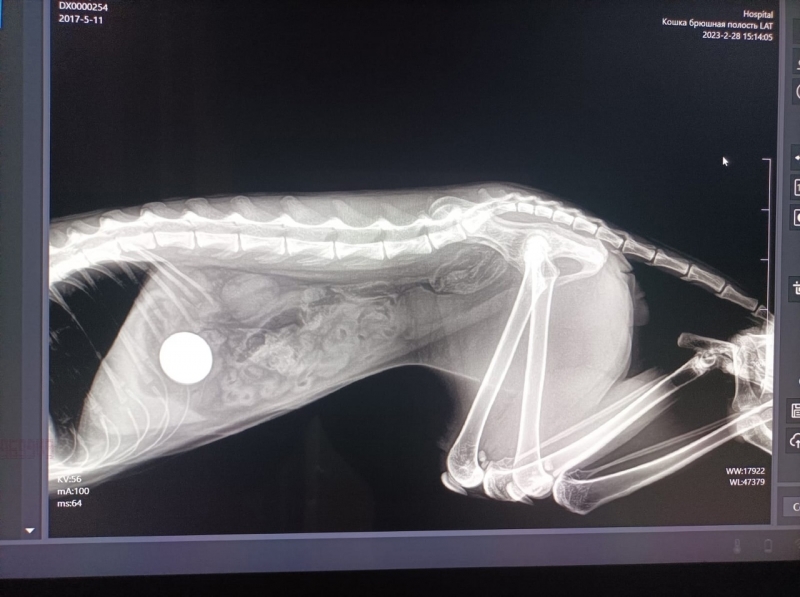

Котик проглотил двухрублевую монету. Операцию по удалению инородного тела из кишечника животного провели специалисты ветстанции.

Хозяева рассказали, что у питомца долгое время было общее недомогание, плохой аппетит, рвота. Обследование и проведение рентгена показало наличие инородного предмета круглой формы. Во время операции извлекли монету, пишет управление Ветеринарии по Вологодской области.